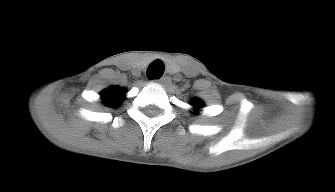

标题: CT22395:左侧肱骨头占位性病灶。 [打印本页]

标题: CT22395:左侧肱骨头占位性病灶。

这是一个17岁的花季少女,在上学期间,自觉左侧肩部不适,家人误以为是外伤引起,没有重视,近日疼痛加剧,来院就诊,ct检查发现如下.

请上传骨窗及x平片。

可能的考虑:骨巨>嗜酸性肉芽肿>软骨母>abc。

建议mri进一步检查。